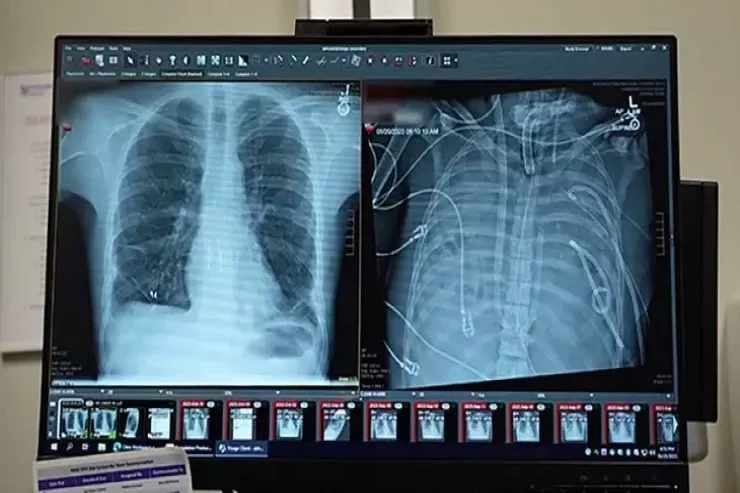

Pasiyent 2023-cü ildə mövsümi qrip keçirən 33 yaşlı kişidir. Xəstəlik qısa müddətdə ağır tənəffüs çatışmazlığına çevrilib və ikitərəfli pnevmoniya, sepsis və kəskin respirator distres sindromu ilə ağırlaşıb.

Xilasın açarı ABŞ-ın Şimal-Qərb Universitetinin mütəxəssisləri tərəfindən hazırlanan, TAL kimi tanınan tam süni ağciyər sistemi olub. Bu  texnologiya qaz mübadiləsi funksiyasını öz üzərinə götürərək qanın oksigenlə zənginləşdirilməsini və karbon qazının xaric edilməsini təmin edib, eyni zamanda qan dövranını tənzimləyərək ürəyin üzərindəki ölümcül yükü azaldıb.

Məhz bu sistem cərrahlara hər iki zədələnmiş ağciyəri radikal şəkildə çıxarmağa və uyğun donor orqan tapmaq üçün saatlar qazanmağa imkan verən süni boşluq rolunu oynayıb.

48 saat ərzində pasiyent əvvəllər həyat üçün mümkünsüz sayılan bir vəziyyətdə olub. Onun qanı bədən xaricində oksigenlə zənginləşdirilib, həkimlər isə gələcəyi uğrunda mübarizə aparıb.